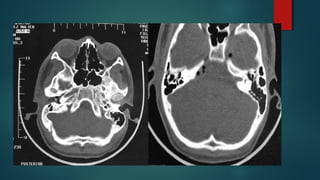

Este documento es el programa para un taller de imágenes del curso de emergencia 2015 impartido por el Dr. Víctor Delgado. El taller se centra en el uso de imágenes médicas para el diagnóstico y tratamiento de pacientes en coma traumático según la base de datos de Marshall. El Dr. Delgado es el único instructor repetido a lo largo del documento.